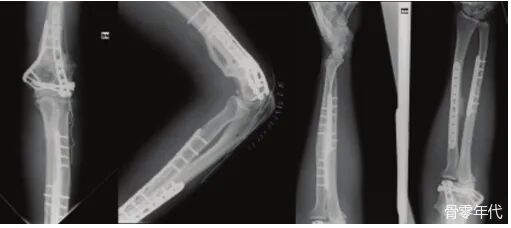

影像学表现